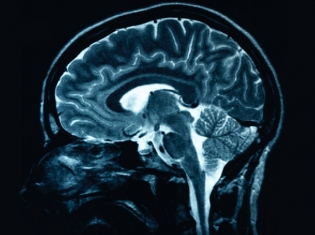

(RxWiki News) A naturally occurring brain protein could lead to better treatments for Alzheimer's disease. Scientists have discovered a "molecular chaperone" - a type of protein that responds to disease - and its ability to kill toxic Alzheimer's tangles in the brain.

This molecular chaperone, HspB1, is a protective mechanism that interferes with the chain of events that causes brain damage in Alzheimer's. Amyloid beta peptide starts the process, clumping in the brain and killing neurons. HspB1 inhibits that process, according to the recent study, published in Molecular and Cellular Biology.

In the brains of people with Alzheimer's, several signs are hallmarks of the disease. Neurofibrillary tangles are fragments of protein within neurons that clog up the cell; neuritic plaques are abnormal clusters of dead and dying brain cells and protein; and senile plaques are areas where the products of dying nerve cells have accumlated.

Amyloid beta peptide plays a major role in these developments in the brain.